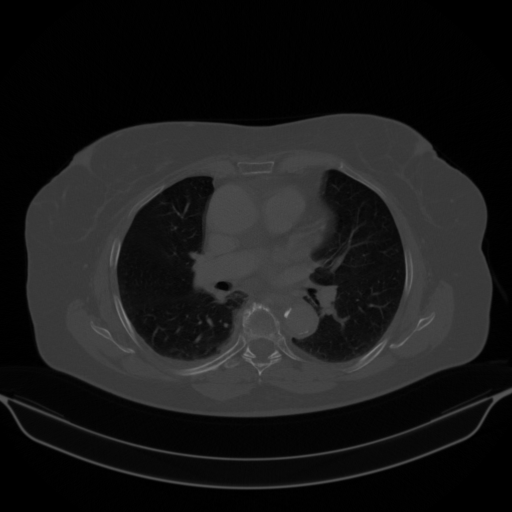

Original NATIVE CT scan (input)

No window - Raw intensity values

Lung window (WL -600, WW 1500 β†’ Low βˆ’1350, High +150)

Mediastinum window (WL 40, WW 400 β†’ Low βˆ’160, High +240)